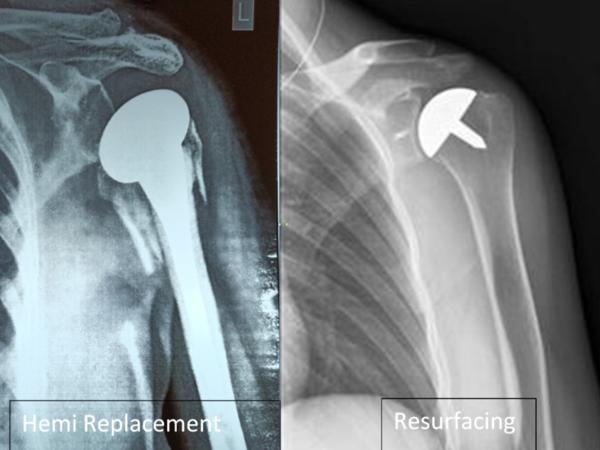

Reverse Shoulder Replacement Surgery

Reverse Shoulder Replacement Surgery By Dr. Palash Gupta Fellowship-Trained Joint Replacement Surgeon – Germany | New Zealand Yatharth Super Speciality Hospital, Model Town | Rohini Clinic, New Delhi 💡 What is Reverse Shoulder Replacement? Reverse Shoulder Replacement is an advanced surgical procedure used to treat complex shoulder problems, especially when the rotator cuff muscles are severely damaged or torn. Unlike traditional shoulder replacement (where the ball-and-socket structure is kept as-is), in reverse shoulder arthroplasty, the positions are reversed: A metal ball is placed on the shoulder socket A plastic socket is attached to the upper arm bone This unique design allows the deltoid muscle to take over the function of the damaged rotator cuff, enabling the patient to regain arm movement. 🤕 Who Needs Reverse Shoulder Replacement? This surgery is ideal for patients who have: Massive, irreparable rotator cuff tears Rotator cuff tear arthropathy (arthritis due to torn rotator cuff) Failed previous shoulder surgeries Complex shoulder fractures (especially in elderly patients) Severe shoulder arthritis with muscle dysfunction ⚙️ How is it Different from Regular Shoulder Replacement? Traditional Shoulder Replacement Reverse Shoulder Replacement Requires healthy rotator cuff Uses deltoid muscle instead Suitable for arthritis without cuff tears Best for cuff tear arthropathy or failed surgeries Ball is on upper arm, socket on shoulder Ball is on shoulder, socket on upper arm 🛌 What to Expect During Surgery Surgical Time: Around 2 hours Hospital Stay: 2–4 days Rehabilitation: Begins early with physiotherapy Recovery Time: 3–6 months for full function Post-op Care: Sling support for 3–4 weeks, followed by structured exercises ✅ Benefits of Reverse Shoulder Replacement Significant pain relief Improved arm function even without rotator cuff Restores ability to perform daily activities (eating, dressing, reaching) Effective solution when other surgeries have failed ⚠️ Are There Any Limitations? Lifelong lifting restrictions (usually up to 5–7 kg) May not restore full range of motion As with any joint replacement, there is a small risk of infection, implant loosening, or nerve injury However, proper surgical technique and post-operative care minimize these risks. 👨‍⚕️ Dr. Palash Gupta: Expert in Complex Shoulder Surgeries With international fellowships in Germany and New Zealand, Dr. Palash Gupta is among the few orthopedic surgeons in Delhi with extensive experience in Reverse Shoulder Arthroplasty. ✅ Advanced training in shoulder joint reconstruction ✅ Uses latest-generation implants for long-lasting results ✅ Personalized rehab programs for faster recovery ✅ Trusted name in revision and complex joint replacement surgeries 📍 Clinic Address: 190, Pocket-D 14, Sector 7, Opp. Metro Pillar No. 415, Rohini, New Delhi – 110085 🏥 Also Practicing at: Yatharth Super Speciality Hospital, Model Town, New Delhi 📞 Book Your Appointment Today Don’t let chronic shoulder pain limit your life. Explore whether Reverse Shoulder Replacement is right for you.